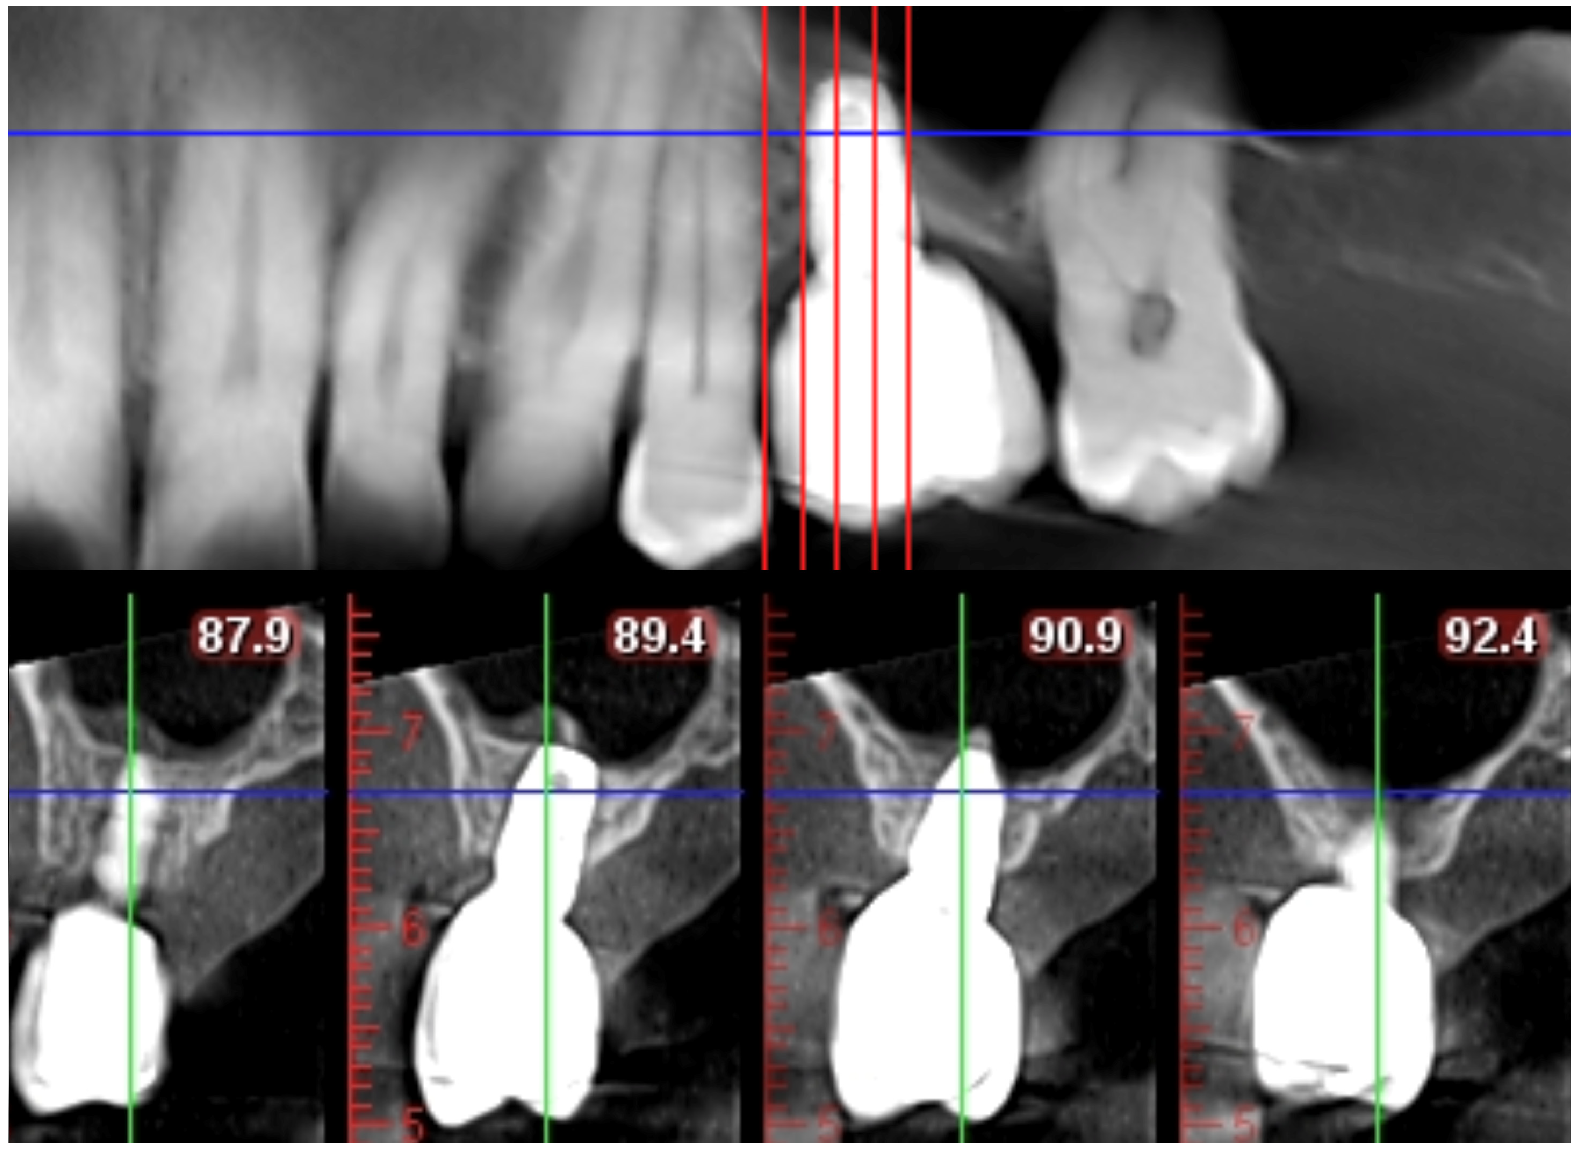

| Case | Age (Years) | Site UNS a | Protocol | Implant Type | SW b (mm) | RBH c (b-p mm) | LIP d (b-p mm) | RBH2 e (b-p mm) | F-U f (Months) | ∆RBH g (b-p mm) |

|---|---|---|---|---|---|---|---|---|---|---|

| 1 | 64 | 14 | No | DS i Profile EV | 10.2 | 3.8–5.8 | 2.0–3.8 | 6.2–8.0 | 57 | 2.4–2.2 |

| 2 | 61 | 4 | No | DS i Astra Tech EV | 11.6 | 3.8–5.0 | 2.0–4.0 | 6.1–8.0 | 48 | 2.3–3.0 |

| 3 | 61 | 15 | No | DS i Profile EV | 12.4 | 3.4–4.1 | 5.0–6.0 | 7.6–8.1 | 4 | 4.2–4.0 |

| 4 | 60 | 3 | Yes | DS i Prime Taper EV | 8.6 | 3.2–6.2 | 5.5–3.5 | 7.8–8.1 | 19 | 4.6–1.9 |

| 5 h | 51 | 3 | Yes | DS i Prime Taper EV | 8.0 | 4.0–7.0 | 2.0–2.5 | 8.0–8.2 | 10 | 4.0–1.2 |

| 6 | 64 | 3 | Yes | DS i Prime Taper EV | 10.4 | 4.2–8.0 | 4.0–4.5 | 8.0–8.8 | 10 | 3.8–0.8 |

| 7 | 65 | 3 | Yes | Biohorizon | 11 | 4.5–5.4 | 3.5–4.0 | 8.6–9.0 | 7 | 4.1–3.6 |

| Tapered Pro | ||||||||||

| 8 | 63 | 14 | Yes | DS i Prime Taper EV | 7.6 | 4.7–8.0 | 0.0–3.0 | 8.0–8.0 | 8.5 | 3.3–0.0 |

| 9 | 64 | 3 | Yes | DS i Prime Taper EV | 11.2 | 3.0–5.1 | 4.0–4.5 | 8.0–8.6 | 6 | 5.0–3.5 |

| 10 | 48 | 4 | Yes | Biomet 3i Prevail | 8.4 | 3.4–4.8 | 2.0–4.5 | 6.8–7.1 | 6 | 3.4–2.3 |

| 11 h | 52 | 14 | Yes | DS i Profile EV | 11.1 | 2.2–4.5 | 3.0–6.0 | 6.2–8.1 | 4.5 | 4.0–3.6 |

| Variable | Site | Min | Max | Mean | Median | Std |

|---|---|---|---|---|---|---|

| RBH | Buccal | 2.2 | 4.7 | 3.7 | 3.8 | 0.7 |

| RBH | Palatal | 4.1 | 8 | 5.8 | 5.4 | 1.4 |

| RBH | Total | 3.4 | 6.4 | 4.7 | 4.7 | 1.0 |

| RBH2 | Buccal | 6.1 | 8.6 | 7.4 | 7.8 | 0.9 |

| RBH2 | Palatal | 7.1 | 9 | 8.3 | 8.1 | 0.5 |

| RBH2 | Total | 7.0 | 8.8 | 7.8 | 8.0 | 0.6 |

| ΔRBH | Buccal | 2.3 | 5 | 3.8 ** | 3.8 | 0.8 |

| ΔRBH | Palatal | 0 | 4 | 2.4 ** | 2.3 | 1.2 |

| ΔRBH | Total | 1.2 | 4.5 | 3.1 ** | 3.0 | 0.9 |